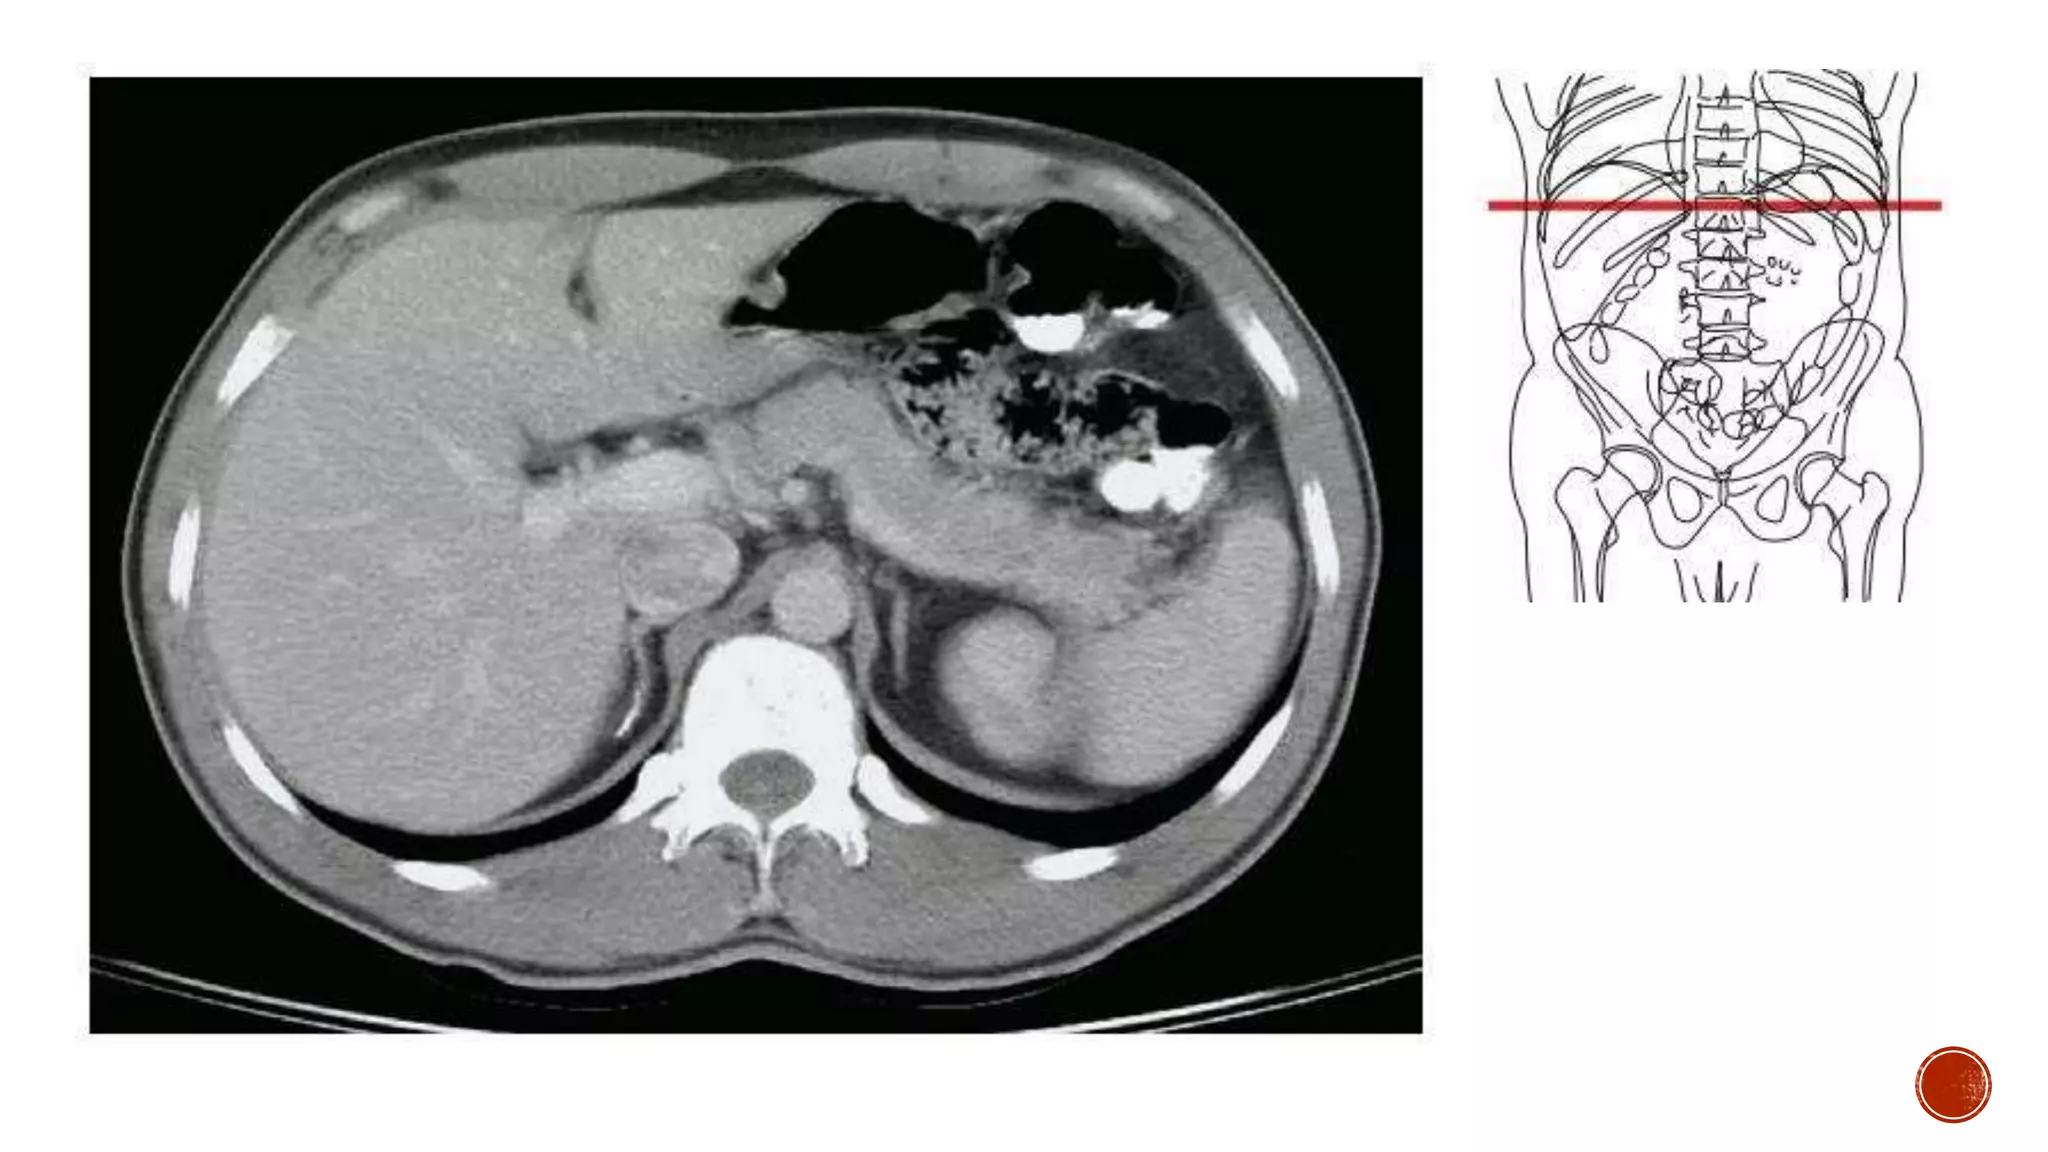

The document describes the anatomy of the abdomen and pelvis region of the human body. It lists over 40 structures and their locations, including major organs like the liver, kidneys, intestines, blood vessels and muscles of the abdominal wall and pelvis. The structures are grouped into sections focusing on different anatomical areas like the abdomen, retroperitoneum, pelvis and gluteal region.